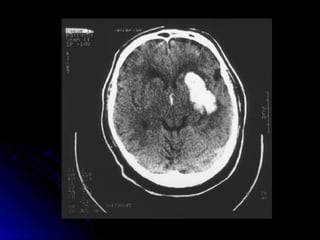

HEMORRAGIA

AVE HEMORRAGICO

“Cuadro causado por

rupt ur a vascular e

irrupción de sangre en el

parénquima cerebral,

acompañado de

hipert ensión endocraneana

y por lo gener al

AVE Hemorrágico

Frecuencia15%

Edades: hombres50-70 años

( 16% antesdelos45)

Mortalidad: 20%, aumentacon

Clasificación HemorragiaCerebral

Iº Gran hemorragiaClásica

IIº HematomaIntraparenquimatoso

1) Profundo 60%

2) Superficial 20%

3) Cerebelo <15%

4) Tronco <5%

IIIº HemorragiaSubaracnoidea 5-10 %